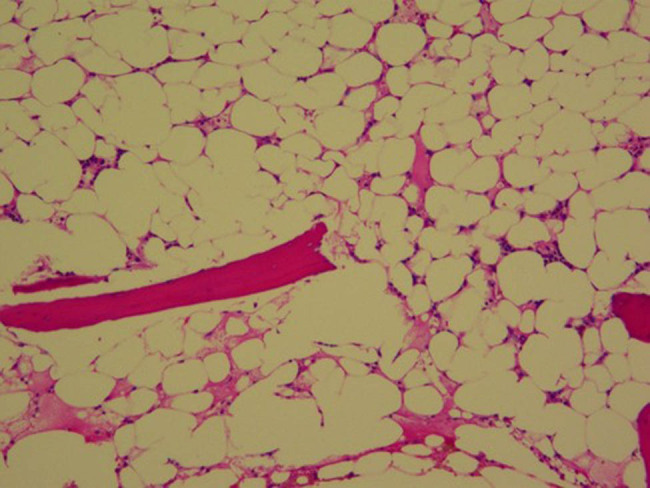

严重再生障碍性贫血(SAA)和鼻咽癌(NPC)是两种不同的疾病,如果不及时治疗,将危及生命。SAA和NPC同时发生是罕见的,并且呈现出一个复杂的治疗悖论。本研究报告了一个诊断为SAA和NPC的独特病例。患者最初接受单倍体造血干细胞移植(HSCT)以实现血液系统快速恢复,随后接受尼莫单抗+放疗治疗癌症。该病例提示,序贯单倍体HSCT和放疗可能是同时存在SAA和NPC患者的一种有希望的治疗策略。

Severe aplastic anemia (SAA) and nasopharyngeal carcinoma (NPC) are two different diseases and are life-threatening if left untreated. The co-occurrence of SAA and NPC is rare and presents a complex therapeutic paradox. This study reports a unique case of a patient diagnosed with both SAA and NPC. The patient initially underwent haploidentical hematopoietic stem cell transplantation (HSCT) to achieve rapid hematologic recovery, followed by nimotuzumab + radiotherapy for carcinoma treatment. This case suggests that sequential haploidentical HSCT and radiotherapy may represent a promising therapeutic strategy for patients with coexisting SAA and NPC.